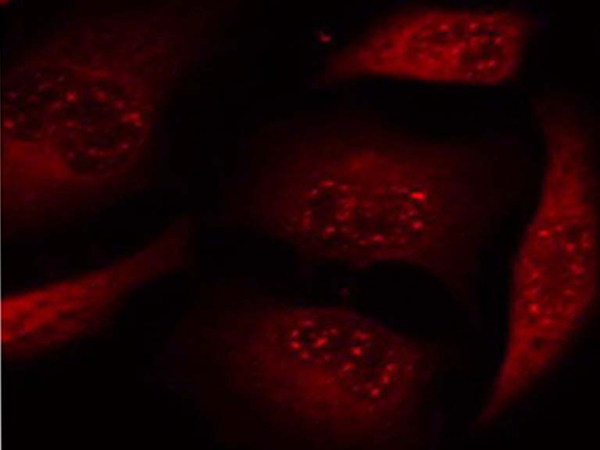

IF positive control: |

Hela cells |

IF Recommend dilution: |

100-200 |